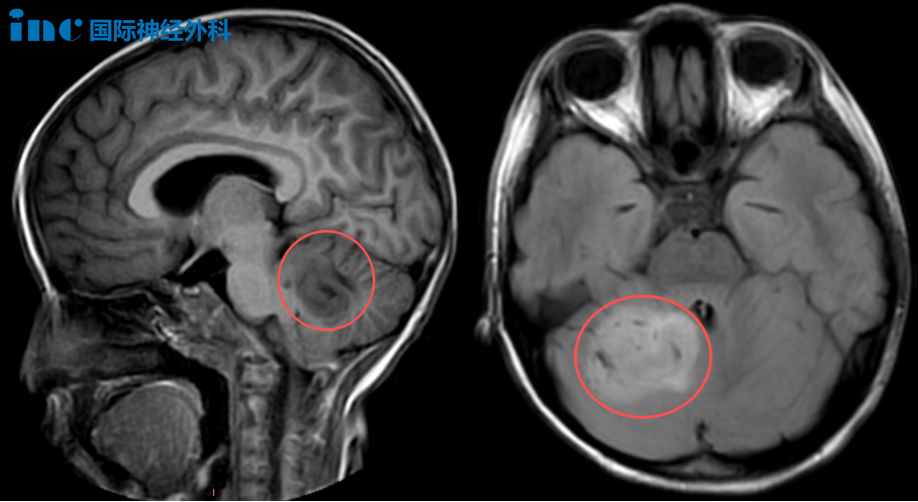

6岁女性患儿乐乐,一个月前经检查发现小脑占位性病变,这一诊断曾使患儿家庭陷入迷茫与无助状态。MRI影像显示较大体积肿瘤,患儿临床表现包括头晕头痛、嗜睡等症状,与原本活泼开朗的状态形成明显对比。导致该临床症状的病因未能及时明确,对患儿父母造成长期困扰。

一个月后,患儿等到巴教授诊治。巴教授术前评估表示:"手术对我来说并非难事,我能完成!"当天上午,巴教授主刀,与苏州大学附属儿童医院神经外科团队协作,应用术中导航及术中超声技术,仔细确认肿瘤边界,最终为患儿顺利实施手术。